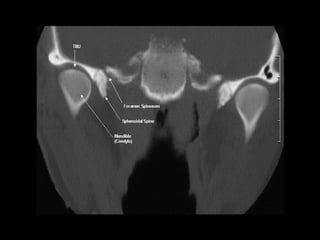

Radiographers use medical imaging equipment like X-rays and MRIs to produce images of patients' internal structures and organs. They are responsible for positioning patients, operating scanning machines, and ensuring quality images. Radiographers must have strong attention to detail, excellent communication skills, and the ability to work well under pressure to accurately capture anatomical features and diagnose any abnormalities.